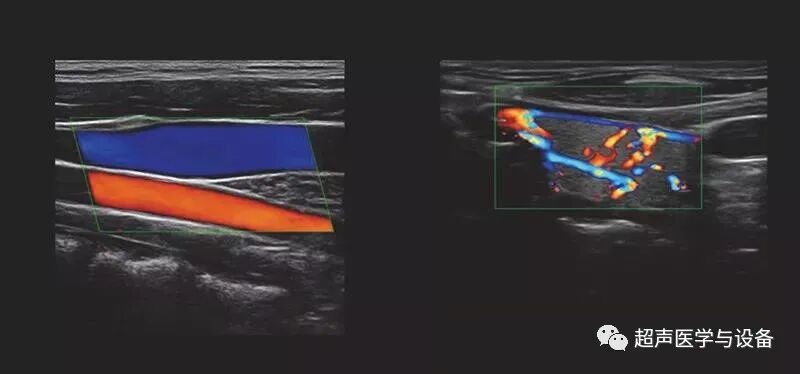

全域血量

通过对彩色采样进行区域分析匹配,区分实质组织和血流型号,对随机噪点进行动态智能检测抑制,得到纯净的彩色血流型号,提升血流检出灵敏度。

图 / 全域血流 Tactile Flow

峰值成像

对感兴趣区域内的血流信号,采取特征强化策略,在单位时间内捕获血流的流

速信息,对血流峰值信号做智能的判断选择,有效增强血流灌注的密度显影,直观

显示肿瘤或可疑病灶的血流分布和血流灌注密度情况。

适用于:

▶ 肿瘤的血流显示;

病灶血流灌注密度差异显示;

微弱血流的时间显示;

动脉壁斑块血流灌注显示